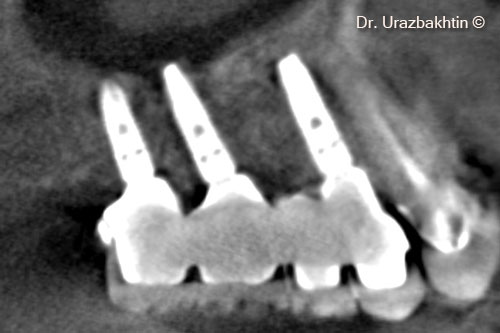

Tăng chiều cao xương hàm bằng kỹ thuật cắt xương ngang vùng hàm

Một bệnh nhân nam (77 tuổi) cần phẫu thuật nâng cao chiều dọc xương hàm.

Sp-block